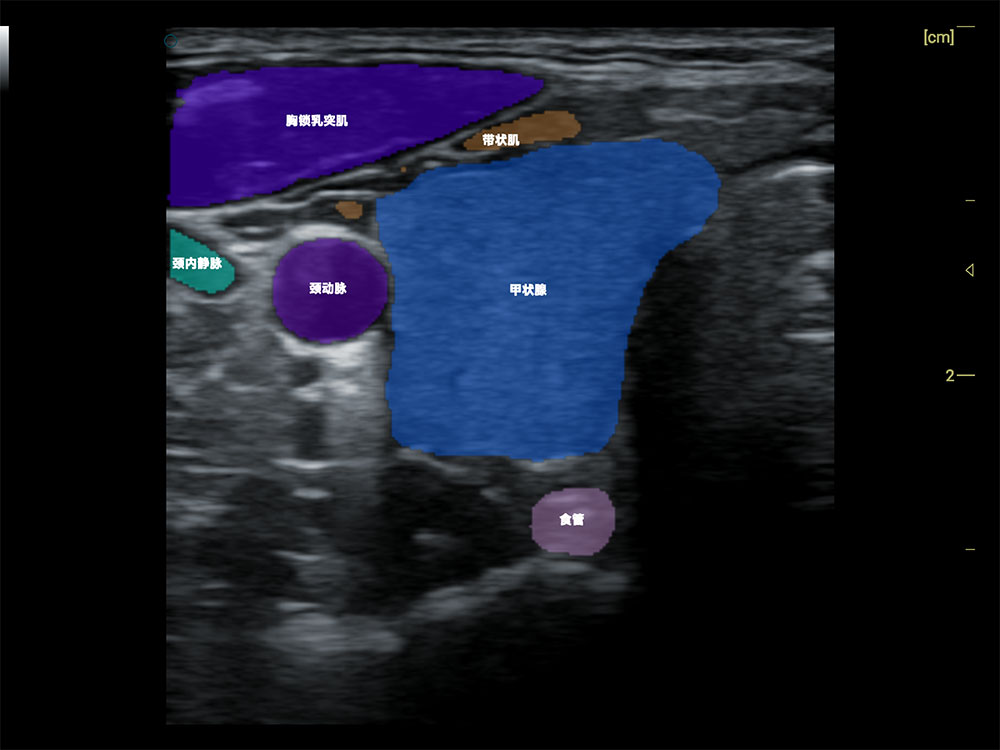

• AI 智能识别甲状腺病灶